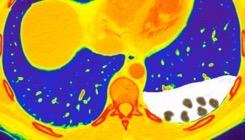

Hemorrágica………….30-70 UH

Extravasación iv. con sangrado activo……….>90 UH

“Simpático”………….,,,,<15 UH

Durso AM et al. Penetrating Thoracic Injury. Radiol Clin N Am 2015.

Urogénico……………….< 15 UH

Entérico.. ………………+/- 15UH

Biliar, Quiloso……………..<0 UH